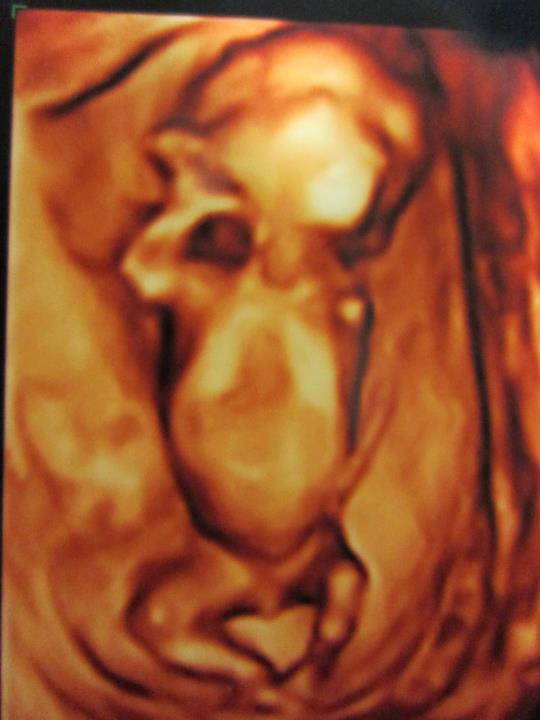

照超音波時寶寶都趴著

每次照超音波時寶寶都剛好趴著,而且還剛好照超音波時給我翻過去,醫生說寶寶趴著,超音波儀器連續動了一陣子還是如此

所以即使已經18W,也無法知道寶寶是DD還是MM